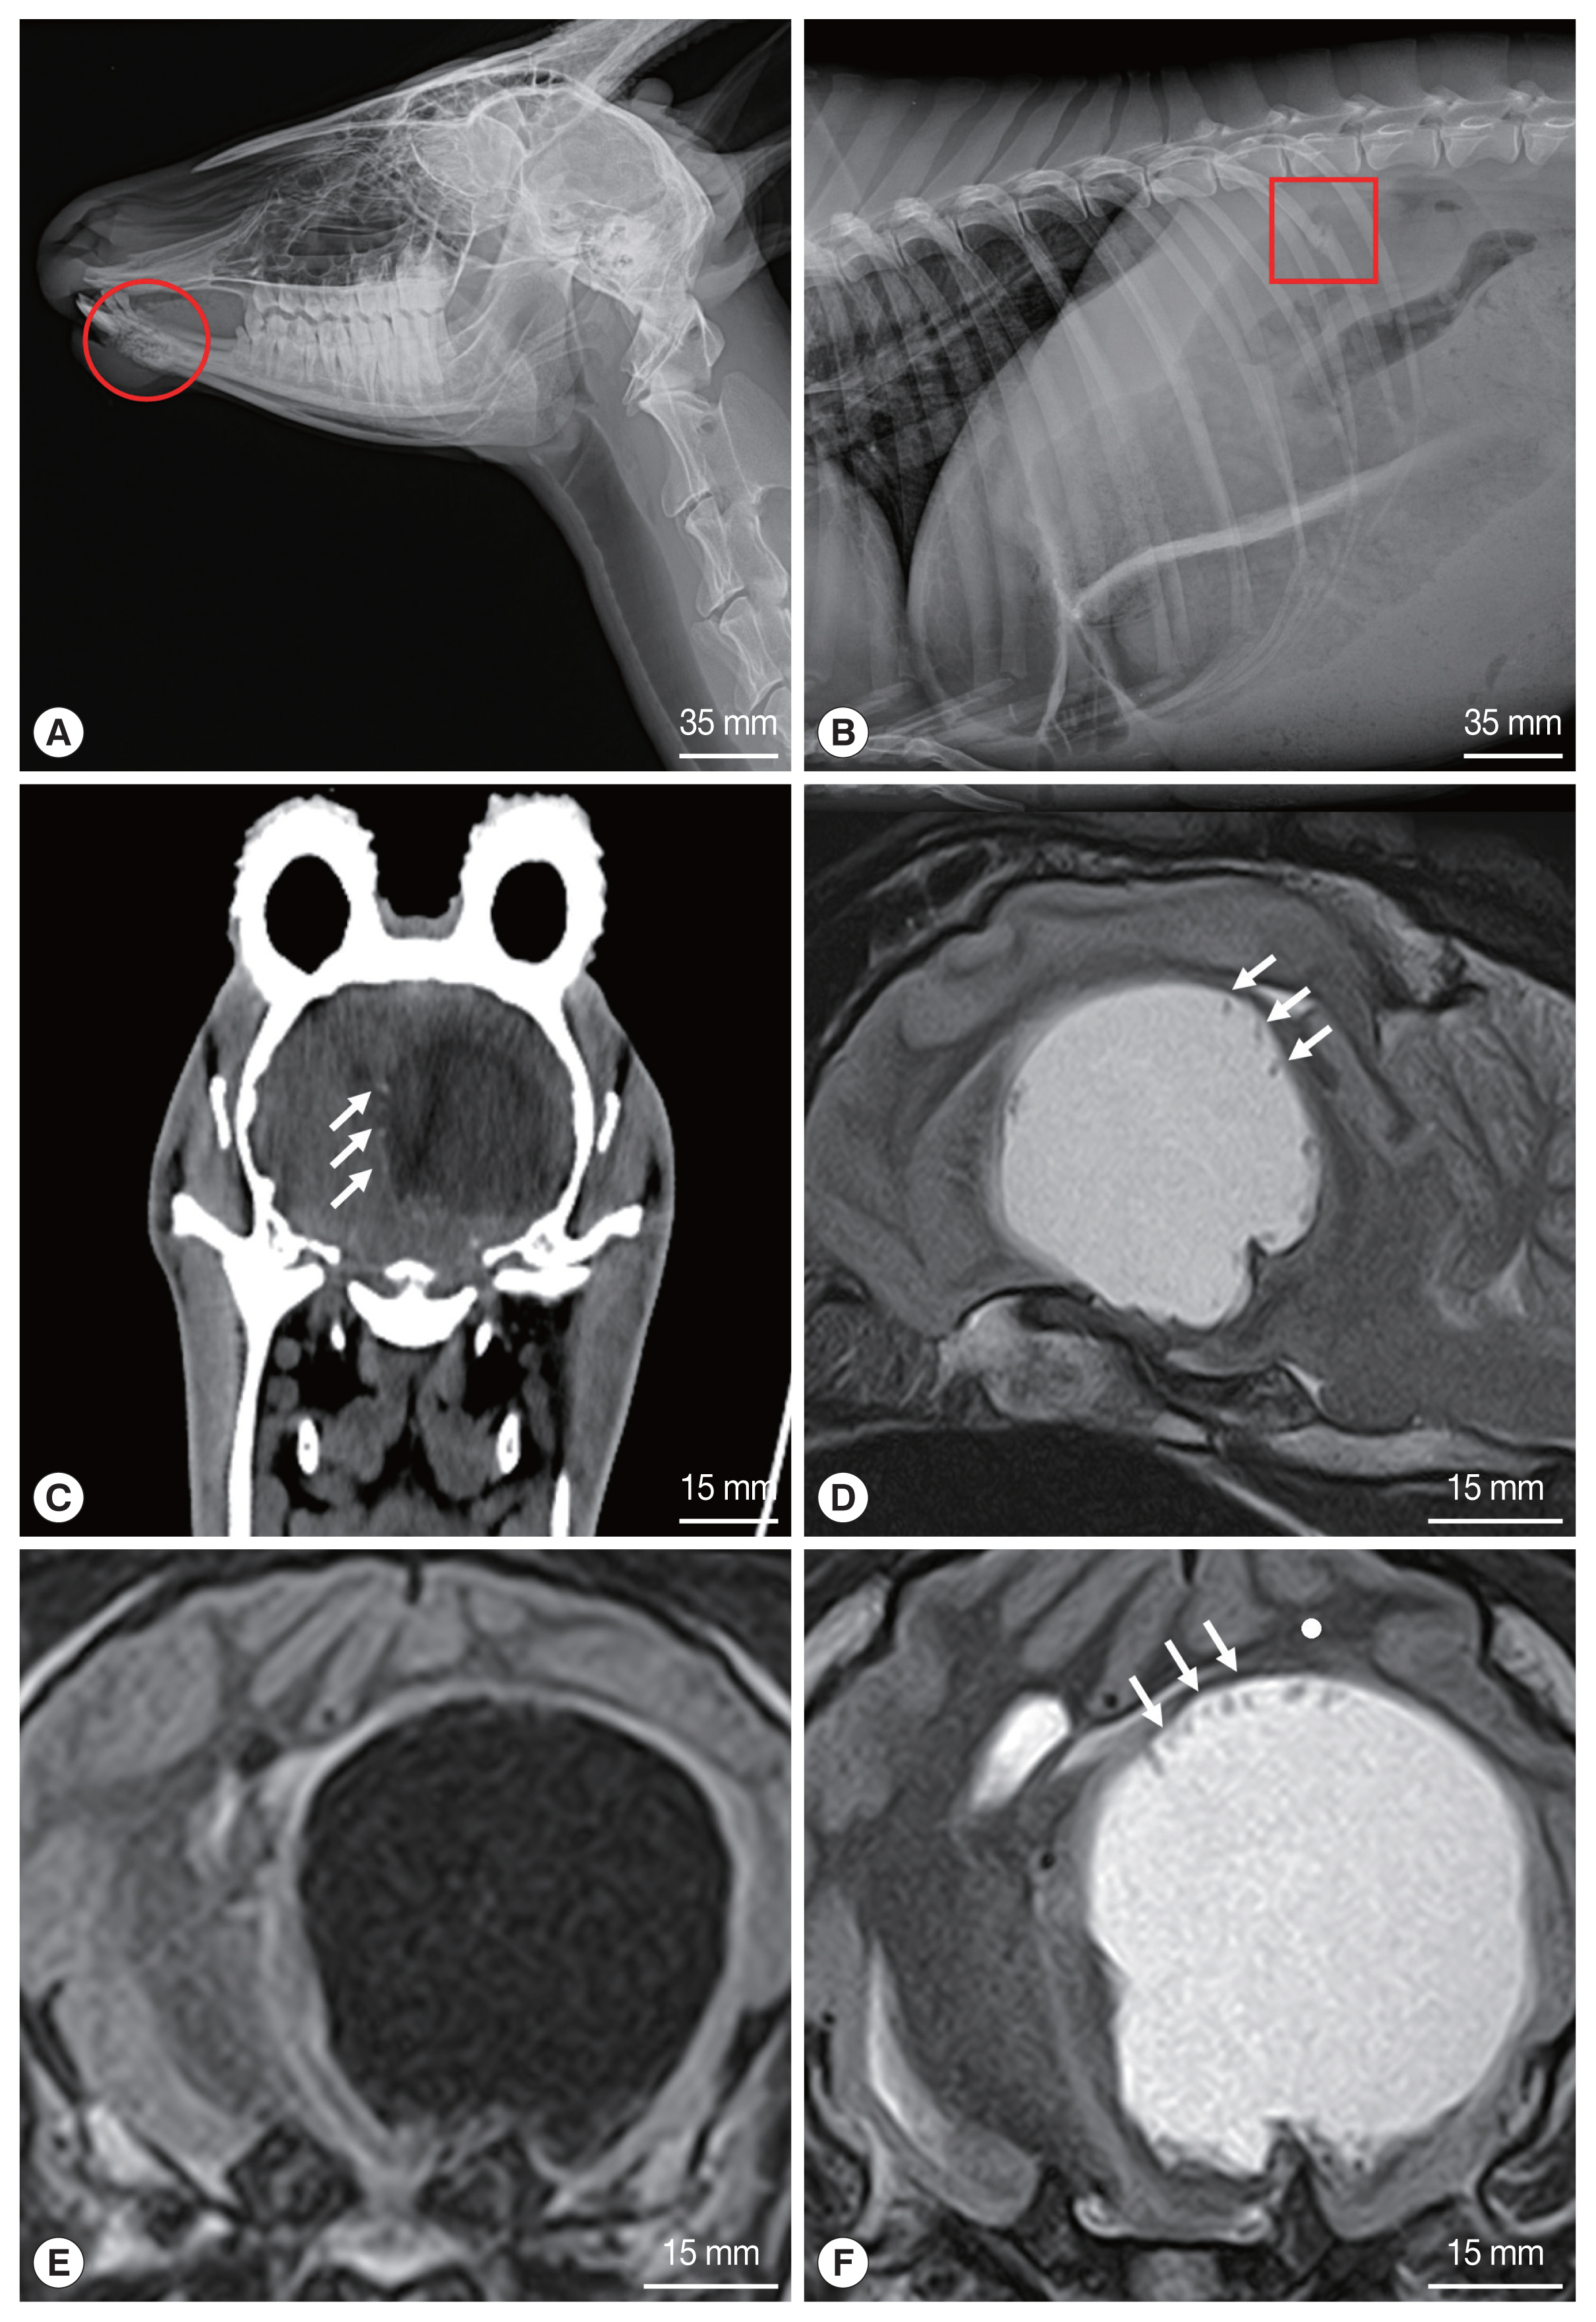

Radiographs of the goral revealed osteolysis of the mandible, fracture of the right 13th rib, and severe pneumonia (Fig. 1A, B). Based on the radiographic findings, the goral was judged to have met a traffic accident (TA), and accordingly treatment was initiated, but the neurological symptoms persisted. CT and MRI of the brain were performed using standard procedures because the neurological symptoms did not improve despite treatment. The goral was positioned in sternal recumbency for CT and MRI examinations. CT scanning was performed using a Somatom Emotion 6 (Siemens, Erlangen, Germany). MRI was performed by a 1.5 T unit (Vantage Elan™, Toshiba, Tokyo, Japan), using a combination of the 16 channel flexible coil (16-channel Flex SPEEDER Large®, Toshiba, Tokyo, Japan) and spine coil (Octave SPEEDER Spine®, Toshiba, Tokyo, Japan). In the CT images, the parasitic cyst (3.1×3.1 cm) was seen as a spherical structure with hypodensity in the left cerebral hemisphere (Fig. 1C). Faint hyperdense structures were also observed at the peripheral margin of the cyst, which were invaginated on the cyst wall (Fig. 1C). MRI of the head demonstrated the presence of a cystic structure in the brain parenchyma of the left cerebral hemisphere (Fig. 1D–F). The cyst was irregular, round shaped and clearly distinguished from the brain parenchyma. The cyst appeared hypointense in the T1 weighted (T1W) image (Fig. 1E) and hyperintense in the T2 weighted (T2W) image (Fig. 1D, F). In the T2W image, hypodense structures were found at the peripheral edge of the cyst inner wall (Fig. 1D, F), but not in the T1W image. Two days after MRI scan, the goral’s clinical signs became severe with heavier breathing, shortness of breath, and eventually the goral died.

Other diagnostic methods such as CT and MRI have also been used to diagnose. CT was used in the diagnosis of coenurosis in humans and other animals. Several scholars have reported that the cyst appears to be a hypoattenuating structure with a mass effect in the CT images [10]. The MRI images of the brain parenchyma infected with Coenurus cerebralis appear hypointense in the T1W image and hyperintense in the T2W image [12]. CT and MRI are diagnostic methods that can accurately determine the exact location and size of the cyst. This information is essential for the surgical removal of the parasitic cysts [10]. In our case, hypointense cyst was detected in the left cerebral hemisphere on CT examination. In the T1W image, the cyst appeared hypointense, while in the T2W image it appeared hyperintense. In addition, the hypodense structures seen at the edge of the cyst inner wall on the CT and MRI images of gorals were determined to be protoscolices of C. cerebralis through post-mortem examination. To the best of our knowledge, in previous reported cases, protoscolices were frequently observed on CT, but not on MRI. However, protoscolices were observed in both MRI and CT in this study.

Fig. 1

Radiographs of the rescued goral. (A) osteolysis of the mandible (circle) and (B) fracture of the right 13th rib (square). CT and MRI of the brain. (C) Transverse CT shows a parasitic cyst located in the left cerebral hemisphere. (D) Sagittal MRI of the brain (T2-weighted). (E) Transverse T1 and (F) T2 weighted MRI. Note an enhanced rim on the periphery of the cyst in C, D, and F. white arrows indicate a protoscolex clusters.

Fig. 1 Radiographs of the rescued goral. (A) osteolysis of the mandible (circle) and (B) fracture of the right 13th rib (square). CT and MRI of the brain. (C) Transverse CT shows a parasitic cyst located in the left cerebral hemisphere. (D) Sagittal MRI of the brain (T2-weighted). (E) Transverse T1 and (F) T2 weighted MRI. Note an enhanced rim on the periphery of the cyst in C, D, and F. white arrows indicate a protoscolex clusters.